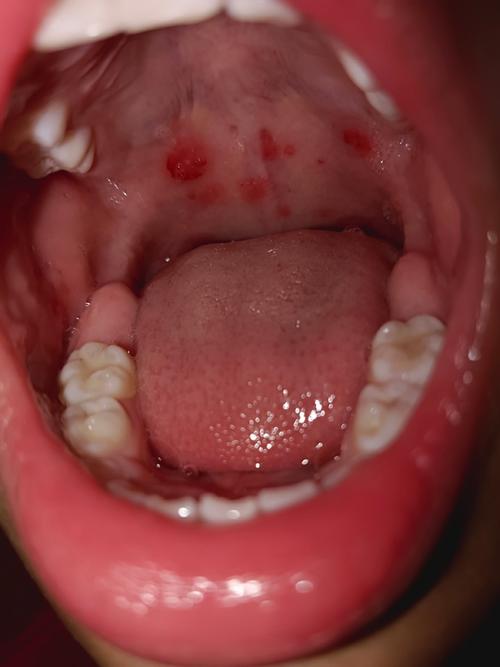

- 口腔水泡/溃疡: 在喉咙、舌、颊粘膜、上颚等处出现小水泡,水泡破溃后形成溃疡,孩子会非常疼痛,导致流口水、拒食、哭闹。

疱疹性咽峡炎

这也是由柯萨奇病毒等肠道病毒引起的,可以看作是手足口病的一种“轻型”或“特殊类型”。

- 口腔水泡/溃疡: 症状非常明显,集中在咽峡部,即扁桃体、软腭、悬雍垂(小舌头)等后咽部位置,溃疡会引起剧烈的咽痛。